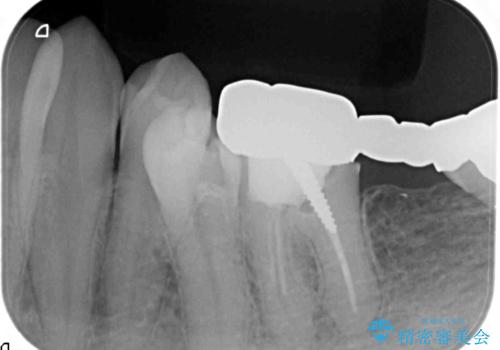

最後方臼歯のインプラント補綴

- 40万円(ストローマンインプラント・カスタムチタンアバットメント・メタルボンドクラウン)費用は治療当時の料金となります

最後方臼歯の治療について

最後方臼歯を喪失した場合、入れ歯・インプラントによる咬合機能回復方法があります。

今回はしっかりと噛むことができ、取り外しの必要のないインプラントによる補綴を行いました。